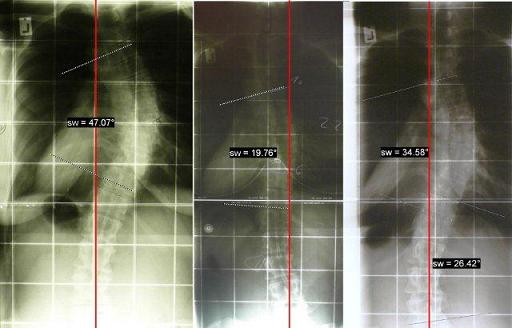

Hier zur Veranschaulichung mein Röntgenverlauf von Januar 2010 (links), über September 2010 (im Korsett) bis August 2011 (72h ohne Korsett).

1. Um zu sehen, wie sich meine Wirbelsäule im letzten Jahr durch konsequentes Korsett-Tragen verändert hat, wurde ich nach 72 Stunden ohne Korsett geröntgt. Das Ergebnis ist superklasse!

Die Rotation hat sich deutlich gebessert, die Rippen stehen besser und meine Krümmung ist unter 40°. Da soll noch jemand sagen, dass eine Korsett-Therapie bei Erwachsenen nichts mehr bringt... Ich bin schmerzfrei, meine Optik hat sich deutlich verbessert und nun habe ich schwarz auf weiß (bzw. weiß auf schwarz), dass selbst radiologisch auch mit über 30 Jahren noch eine deutliche Korrektur möglich ist.